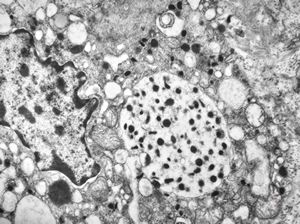

F, 71y. | carcinoid … metastasis to lymphonode